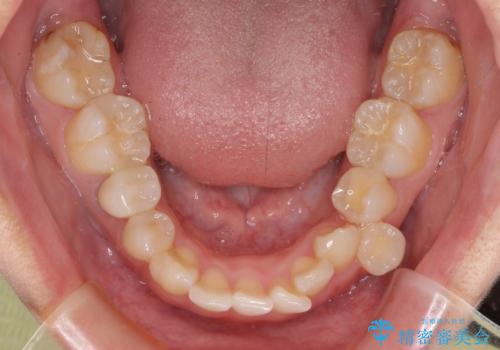

- 下顎の歯列から飛び出した小臼歯を気にして来院された患者様です。

歯列以外に、上顎左右側切歯が矮小歯であり、上顎4前歯は失活していたため、矯正治療で歯列を整えるとともに上顎前歯の幅を調整し、矯正治療後にオールセラミッククラウンにて審美歯科治療を行うこととしました。

下顎の小臼歯を移動しきるのに2年弱の期間を要することとなり、補綴治療も合わせて2年半ほどの治療期間となりました。